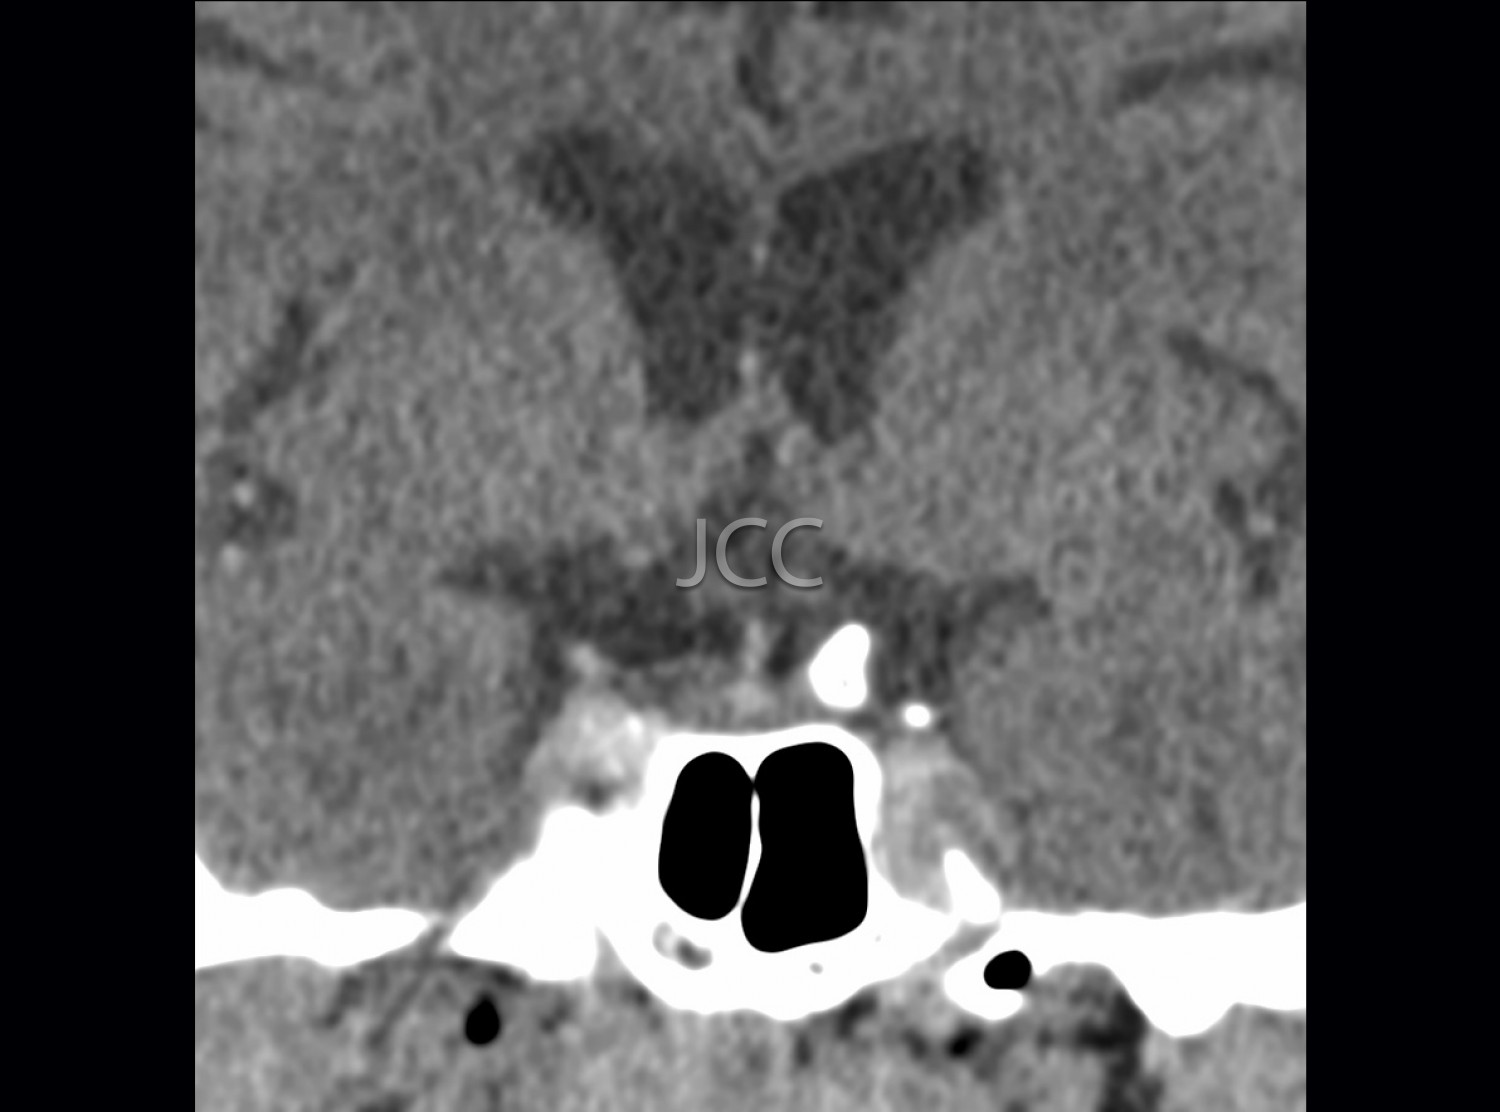

Computed Axial Tomography - Pituitary CAT scan

Computed Axial Tomography (CAT) - Dual Energy - 256 slices is a diagnostic technique that allows the evaluation of various parts of the human body, including the lungs, liver, pancreas, kidneys, heart, vascular structures and bone structures.